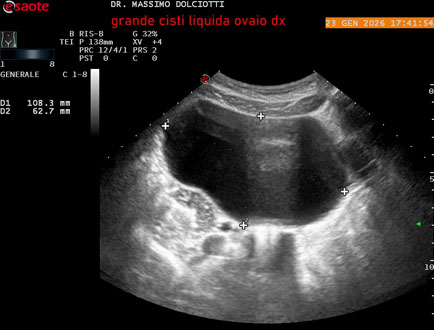

Età Paziente: F 29 anni

Motivazione dell'esame: dolore al lato destro della pelvi in portarice di cisti liquida all'ovaio destro.

Commento all'esame: le immagini ed il video documentano, in sede pelvica, grande formazione anecogena, delle dimensioni di 110 x 60 mm, priva di vascolarizzazione, da ricondurre a grande cisti liquida dell'ovaio destro.

Conclusioni: grande cisti liquida all'ovaio destro (large fluid cyst on the right ovary).